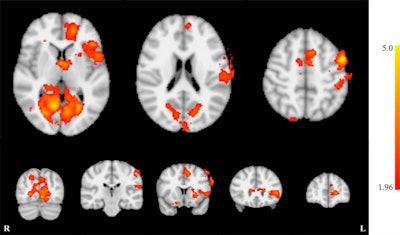

The source of tinnitus has been linked to the primary auditory cortex, the part of the brain where sounds are processed. So researchers from Wright State University in Fairborn, OH, led by Matthew Sherwood, PhD, decided to study the use of fMRI echo-planar imaging (EPI) scans of this brain region to measure the effectiveness of a therapy designed to distract tinnitus sufferers from the noise.

The neurofeedback exercise involved exposing the volunteers to alternating periods of white noise while they watched their own brain activity as it was acquired with the fMRI scans, represented by a bar on a screen that measured brain activity. Each training run consisted of a 30-second "relax" period followed by a 30-second "lower" period, in which individuals were asked to try to lower the bar by decreasing activity in their primary auditory cortex.

The volunteers were instructed in techniques designed to reduce brain activity, such as diverting attention from sounds to other sensations like touch and sight. The fMRI scans indicated that the volunteers were able to reduce brain activity through the techniques.

Results from the 18 individuals were then compared with those from a control group of nine people who were given sham neurofeedback: They performed the same attention-diversion tasks, but the bars they were trying to reduce came from a random study participant. This allowed the researchers to see the actual effects of the neurofeedback technique on the primary auditory cortex.